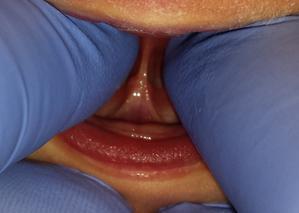

Figure 4 and 5:  This is the exact same patient.  The image on the left shows a submucosal tongue tie and on the right it is shown when upward pressure is placed on the tongue.

Tongue ties come in assorted varieties, shapes, sizes and make-ups.  Some are very easy to see and others are much more difficult to see and need to be physically felt and examined by someone with experience in recognizing, diagnosing and treating these issues.  Tongue ties are very thin and attach to the lower jaw and the tongue will have a small indent at the tip.  Ties can appear further back in the mouth and when the tongue is lifted a webbed appearance may be seen behind the bottom jaw (See Figure 1 and 2 below).  This webbed appearance resembles the Eiffel Tower and restricts the full range of movement of the tongue.  The most difficult types of ties to diagnose and treat are posterior or even further back in the mouth and under the tongue’s mucosal layer (submucosal).  These ties are not easily seen and almost exclusively need to be felt with a finger and assessed through a thorough nursing history and digital sucking exam.  These ties are typically thicker and denser in these posterior areas, resembling a guitar string or piano wire, as opposed to the more thin anterior variety that are more thin and almost transparent from a side view.

Figure 1, 2 and 3:  These pictures show a variety of lingual frenulums or tongue ties in infants.  Notice the varied thickness, degree of webbing, connection points with the tongue and into lower jaw and restriction to tongue elevation.